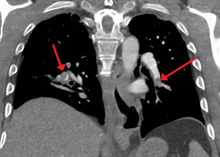

| Chest spiral CT scan with radiocontrast agent showing multiple filling defects both at the bifurcation ("saddle" pulmonary embolism) and in the pulmonary arteries. | |

CT pulmonary angiography (CTPA) is a pulmonary angiogram obtained using computed tomography (CT) with radiocontrast rather than right heart catheterization. Its advantages are clinical equivalence, its non-invasive nature, its greater availability to people, and the possibility of identifying other lung disorders from the differential diagnosis in case there is no pulmonary embolism. Assessing the accuracy of CT pulmonary angiography is hindered by the rapid changes in the number of rows of detectors available in multidetector CT (MDCT) machines.[45] According to a cohort study, single-slice spiral CT may help diagnose detection among people with suspected pulmonary embolism.[46] In this study, the sensitivity was 69% and specificity was 84%. In this study which had a prevalence of detection was 32%, the positive predictive value of 67.0% and negative predictive value of 85.2% (click here to adjust these results for people at higher or lower risk of detection). However, this study's results may be biased due to possible incorporation bias, since the CT scan was the final diagnostic tool in people with pulmonary embolism. The authors noted that a negative single slice CT scan is insufficient to rule out pulmonary embolism on its own. A separate study with a mixture of 4 slice and 16 slice scanners reported a sensitivity of 83% and a specificity of 96%, which means that it is a good test for ruling out a pulmonary embolism if it is not seen on imaging and that it is very good at confirming a pulmonary embolism is present if it is seen. This study noted that additional testing is necessary when the clinical probability is inconsistent with the imaging results.[47] CTPA is non-inferior to VQ scanning, and identifies more emboli (without necessarily improving the outcome) compared to VQ scanning.[48]